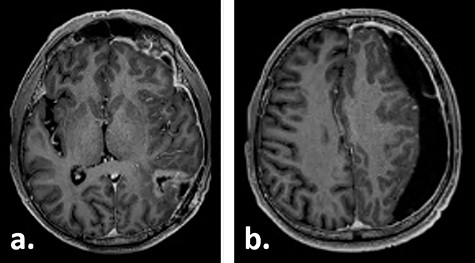

Ten weeks postoperatively, the patient complained of vertigo and a self-limiting episode of right-sided visual field restriction and neglect. Subsequently, oral cortisone therapy was started again, which lead to the relief of these symptoms. The MRI showed a new contrast enhancement around the resection cavity, possibly treatment-related after radiochemotherapy, as well as a 14-mm-thick, left-sided subdural fluid collection causing a midline shift of 6 mm, which was interpreted as a subdural hygroma or hematoma (Fig. 2). The latter was slightly progressive on a CT scan 1 week later, and surgical evacuation through a burr hole was indicated. Intraoperatively, it presented as a slightly xanthochrome, slightly pressurized subdural hygroma. No pathological alterations of the dura were revealed during this procedure. Postoperatively, the subdural hygroma was incompletely regressive and began to grow again as was seen on the CT images 3 weeks after the surgery. This finding was considered to be related to post-radiation changes. The patient stayed asymptomatic and received two cycles of adjuvant chemotherapy with temozolomide 150 mg/m2 body surface area and 200 mg/m2 body surface, respectively.

Gadolinium-enhanced T1-weighted axial MRI of the patient 10 weeks after tumour resection demonstrating the resection cavity (a) and new subdural fluid collection (b).